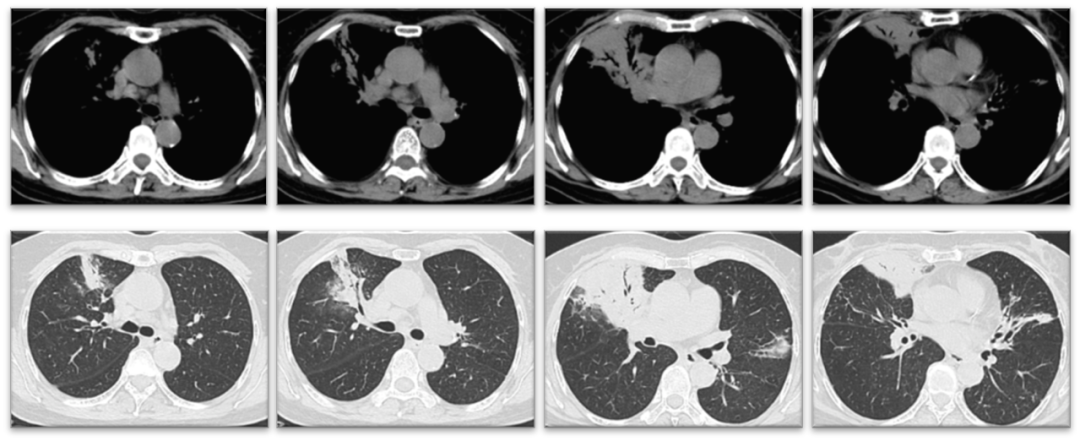

最终诊断患者为支气管扩张合并脓肿分枝杆菌感染,3月8日更换为头孢西丁、阿米卡星、克拉霉素及莫西沙星抗感染,患者体温逐渐恢复正常。2022年3月23日复查胸部CT可见右中肺渗出较前稍好转(图4),继续抗脓肿分枝杆菌治疗。

图4  右中肺渗出较前好转